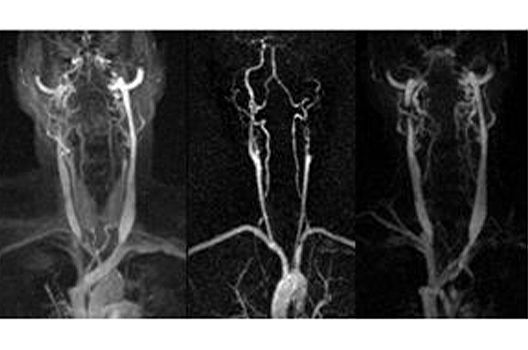

MR-Angiographie

Der ständige Einstrom des Blutes in ein ausgewähltes Volumen oder die zeitweise Beschränkung der Ausbreitung von intravenös gegebenen Kontrastmittel auf die Gefäße kann bei einer geeigneten Wahl der Messsequenzen dazu benutzt werden, Darstellungen von Gefäßen in dem Volumen zu erzeugen. Dabei macht es die Fülle von arteriellen und venösen Gefäßen häufig erforderlich, eine Auswahl bei dieser Darstellung zu treffen, weil sich sonst einzelne kleine Gefäße häufig nicht mehr identifizieren lassen. Die Realisierung einer solchen Auswahl ist abhängig von der Wahl der verwendeten Messtechnik. Bei der Time-of-Flight-Angiographie. die auf dem Einstrom von ungesättigtem Blut in die angeregte Schicht beruht, kann die unterschiedliche Richtung der Flussgeschwindigkeit für eine selektive Sättigung benutzt werden. Wenn der Kontrast in den Gefäßen durch die Gabe von Kontrastmitel produziert wird, kann der zeitliche Verlauf der Kontrastmittelverteilung in den Gefäßen für eine Separierung herangezogen werden.

In einem aktuellen Forschungprojekt soll die Qualität von MR-Angiographien in spezifischen klinischen Fragestellungen durch eine Optimierung von Messparametern und Auswerteverfahren verbessert werden.